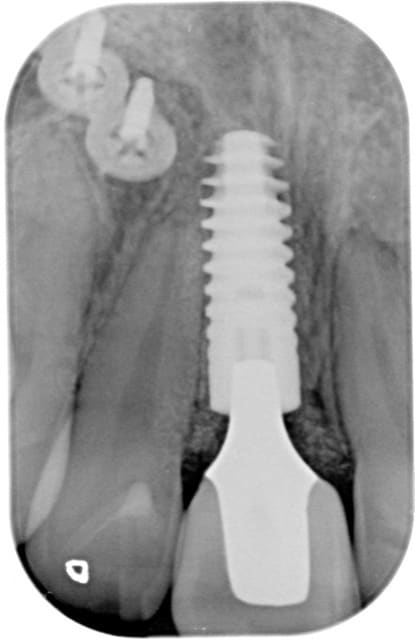

Oui, voici les radios

Pour la 4 (22) au tout début j'avais fait une ccc, mais le collet malgré une chape opaque était grisé, on a donc refait une ccm!

La CCM du 4 se voit facilement, les autres non, et pour cause, soit il y a du Margin (3), soit c'est de la prothèse supra implantaire et il y a donc plus de place en général pour que la prothésiste gère sa stratification et sa morpho